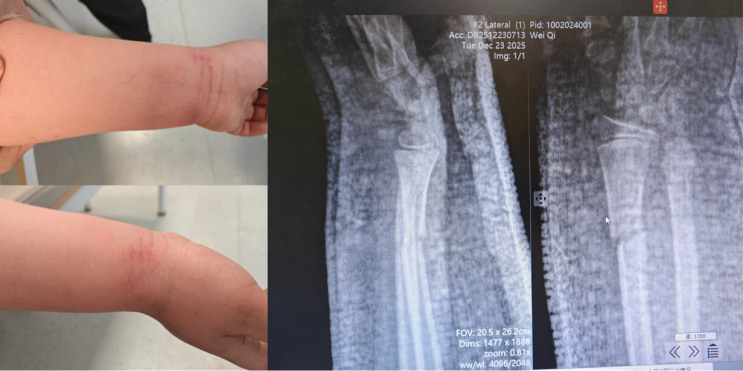

复位操作中,在董博主任与周健副主任医师的指导下,杜龙龙医生先对患儿左腕轻柔持续牵引,缓解骨折嵌顿,再顺着骨骼生理结构精准推挤移位骨端,同步复位脱位关节。董博主任在一旁紧盯患儿的肢体反应,不时提醒:“力道再轻一点,注意观察指尖血运。”周健副主任医师则密切关注骨骼复位的角度,及时给出调整建议。短短几分钟后,随着轻微骨擦音,男孩畸形的腕部逐渐恢复正常。后续石膏固定及复查X线片显示,骨折断端对位对线良好,脱位完全纠正,复位效果超预期。

术后,杜龙龙为家属详细讲解了后续护理要点,董博主任也叮嘱:“儿童骨折愈合快,但也要定期复查,确保骨骼正常生长,我们会全程跟进孩子的康复情况。”看着孩子手腕的肿胀慢慢消退,畸形彻底消失,明明的爸爸激动地握住三位医生的手,连声道谢:“太感谢你们了,红会医院的医生真是妙手回春,让孩子免受手术之苦!”